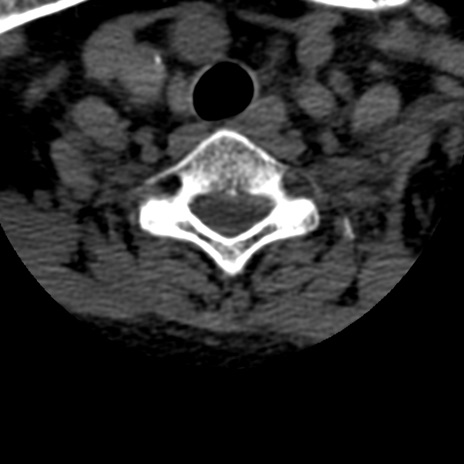

症例50 頚椎CT(横断像)

頚椎CT